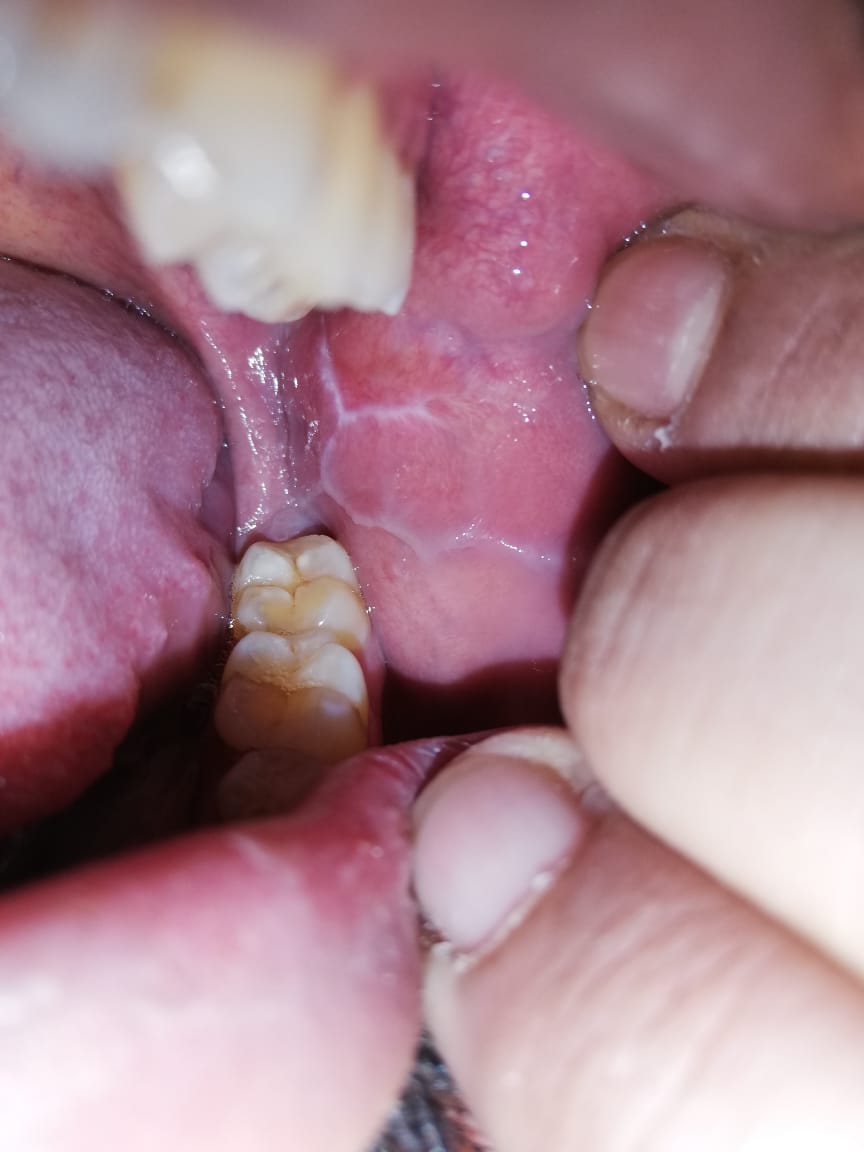

28 yr old male, obese, smoker for ten years, developed white streak like lesion on buccal mucosa and inner lips more than 6 months ago. The lesions have increased in number since. They are painful only sometimes when they come in contact with teeth. No history of dental procedure. Which speciality needs to be referred? Dermatology, dentistry or some other? Which treatment can be used in the meantime?

The D/D is nicotinic stomatitis causes by heavy smoking, keratosis of area may be due to chemical or thermal irritants, the only treatment of it is to quit smoking And the lesion start to regress within 2-3 weeks with proper cleansing and maintaining oral hygiene.. if on quitting of smoking after few weeks the lesion size remain same than there ll be need of the biopsy. If it persists after month following cessation of smoking need to consult oral pathologists or oncologist

First of all you need to consult a Maxillofacial Surgeon (priority)

Secondly, try quite smoking and do warm water rinses with a salt (if BP issues, then w/o salt) 6-8 times a day.

Can't gave you definite diagnosis but could be keratotic white lesion like lichens planus etc. but you must visit Maxillofacial Surgeon for further evaluation

Seems to be cheek bitting at left, will reduce with warm water rinses.